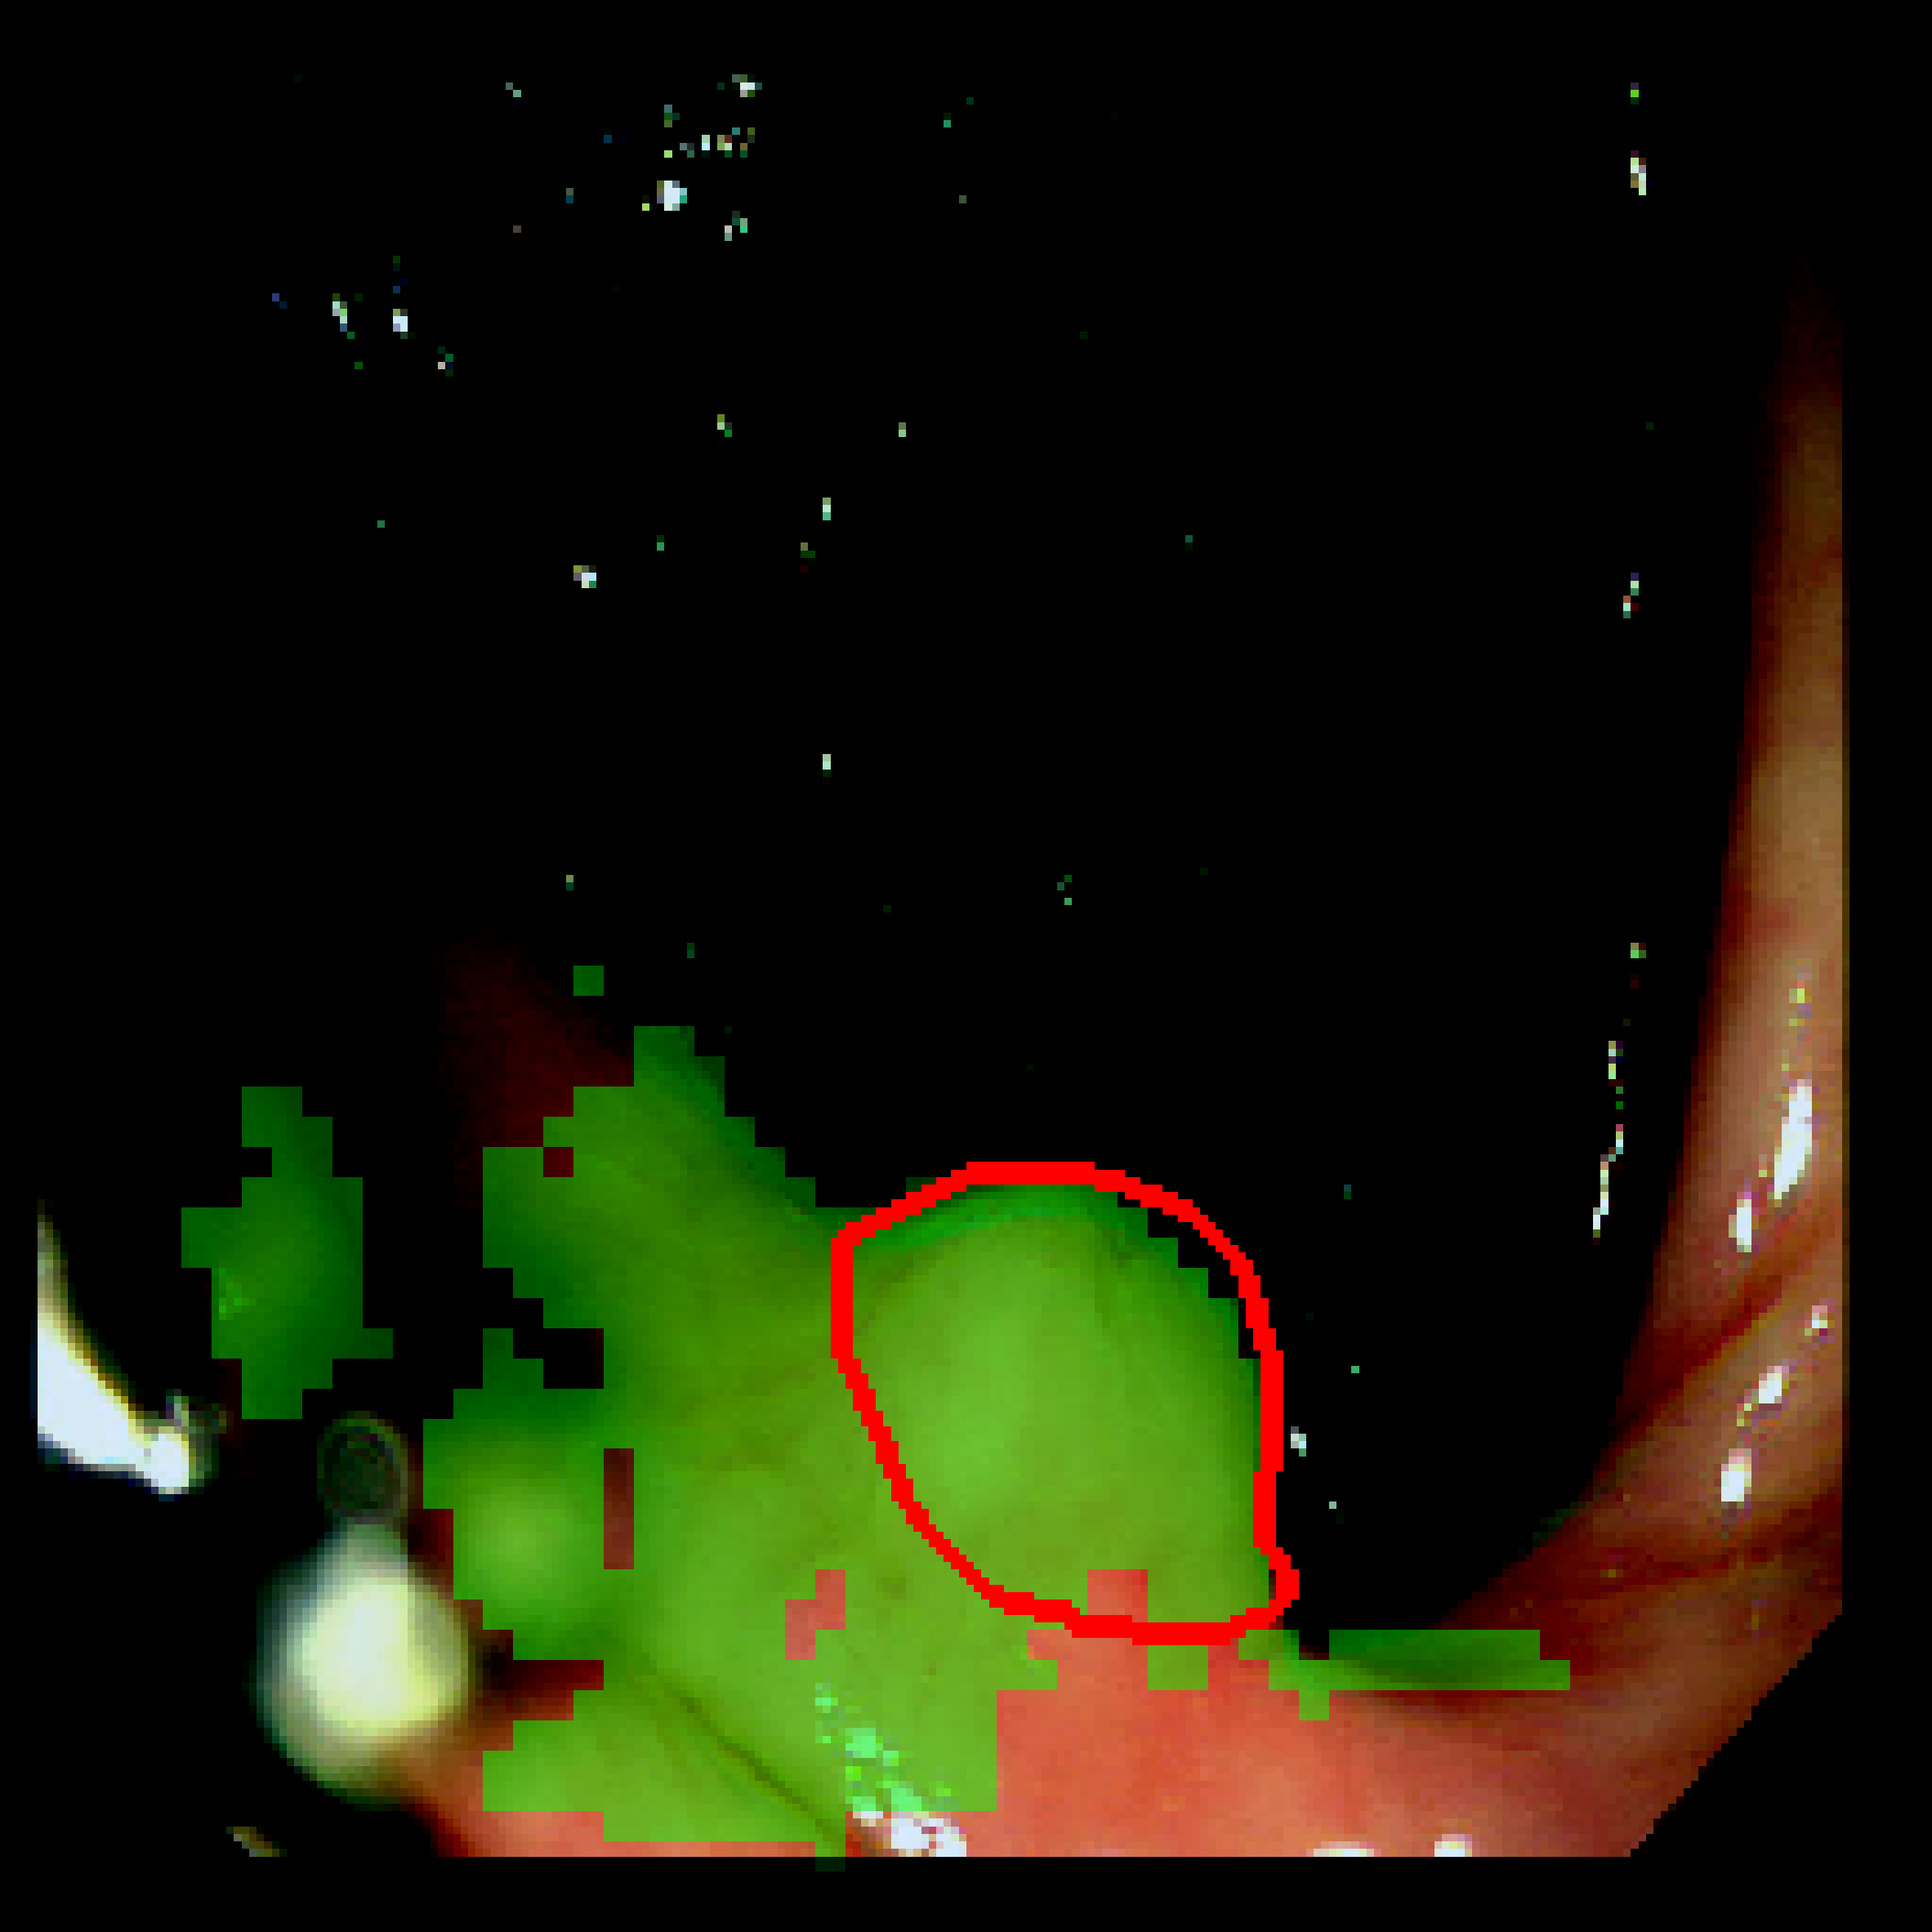

Table 3: Qualitative results of different methods, \Circle and \CIRCLE denote groundtruth and predicted mask, respectively.

SAM MedSAM SAM-Med2D CPC-SAM KnowSAM Ours

5% Promise [Uncaptioned image] [Uncaptioned image] [Uncaptioned image] [Uncaptioned image] [Uncaptioned image] [Uncaptioned image]

10% Promise [Uncaptioned image] [Uncaptioned image] [Uncaptioned image] [Uncaptioned image] [Uncaptioned image] [Uncaptioned image]

5% Colon [Uncaptioned image] [Uncaptioned image] [Uncaptioned image] [Uncaptioned image] [Uncaptioned image] [Uncaptioned image]

10% Colon [Uncaptioned image] [Uncaptioned image] [Uncaptioned image] [Uncaptioned image] [Uncaptioned image] [Uncaptioned image]

For the qualitative results shown in Tab. 3, our method consistently produces more accurate and compact segmentation results for most cases in the PROMISE12 and COLON datasets, effectively capturing the prostate and polyp boundaries while suppressing background noise. In contrast, other approaches tend to over-segment the target regions, leading to the inclusion of irrelevant surrounding tissues. These results visually demonstrate the robustness of our method in handling diverse anatomical variations.